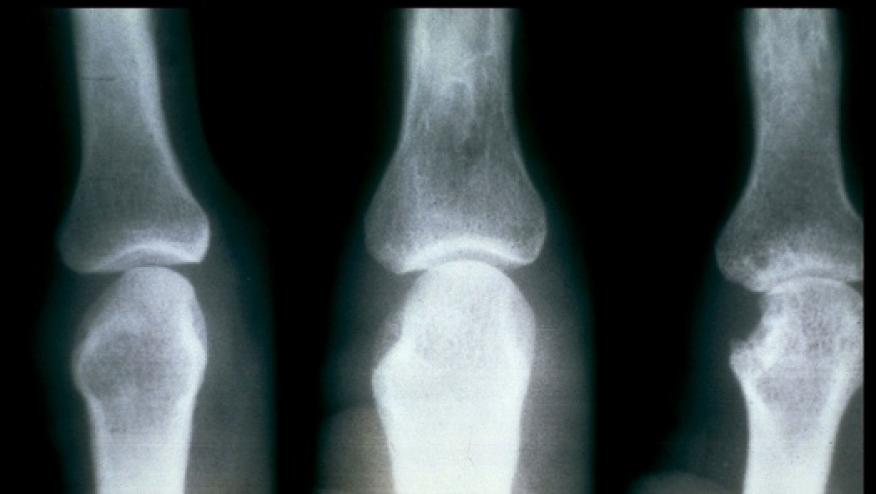

The American College of Rheumatology's (ACR) has published a preview of new research from ACR Convergence 2023 showing that AI and a deep learning system could accurately identify and predict joint space narrowing and erosions in hand radiographs of patients with rheumatoid arthritis (RA). Abstract 0745

For the current study, Hitchon and colleagues aimed to develop and validate a deep learning system for the automated detection of joints and prediction of SvH scores in hand X-rays of patients with RA.